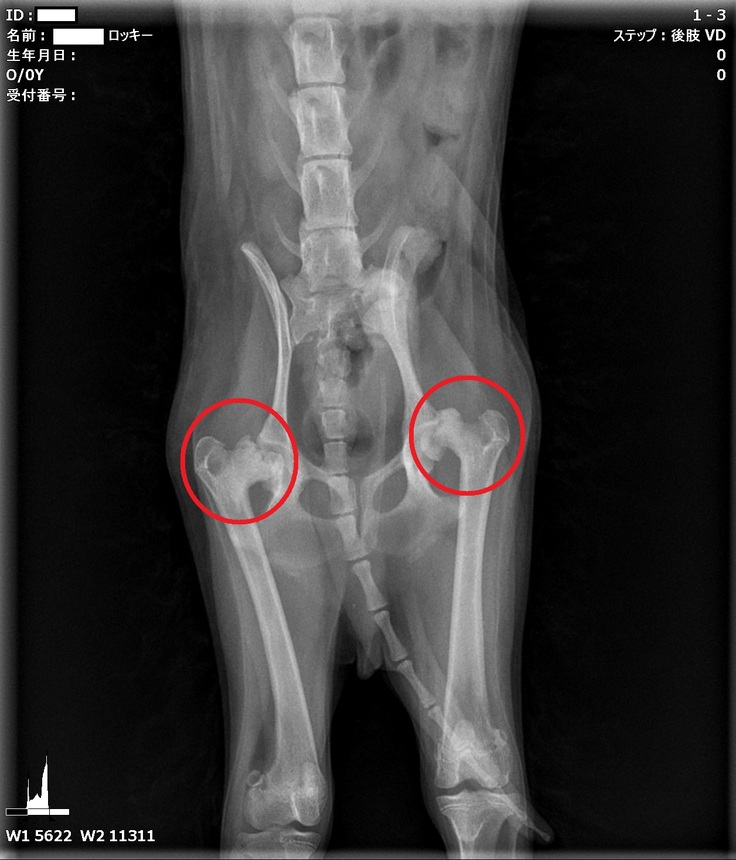

心配でしたので、すぐにかかりつけの動物病院でレントゲンを撮ってもらったところ、

「股関節に異常がありそう」と言われてしまいました。

≪両脚のレッグペルテス≫で【とても状態が悪い】とのことでした。

動物病院2か所で診てもらい、どちらも状態が悪いとの診断で、痛み止めの処方では改善しないと言われてしまいました。

トイプードル♂(9か月)の脚の手術(右後脚と左後脚の大腿骨頭切除関節形成術)をします。